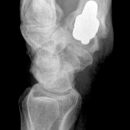

Bennett Fraktur mit geringer Dislokation